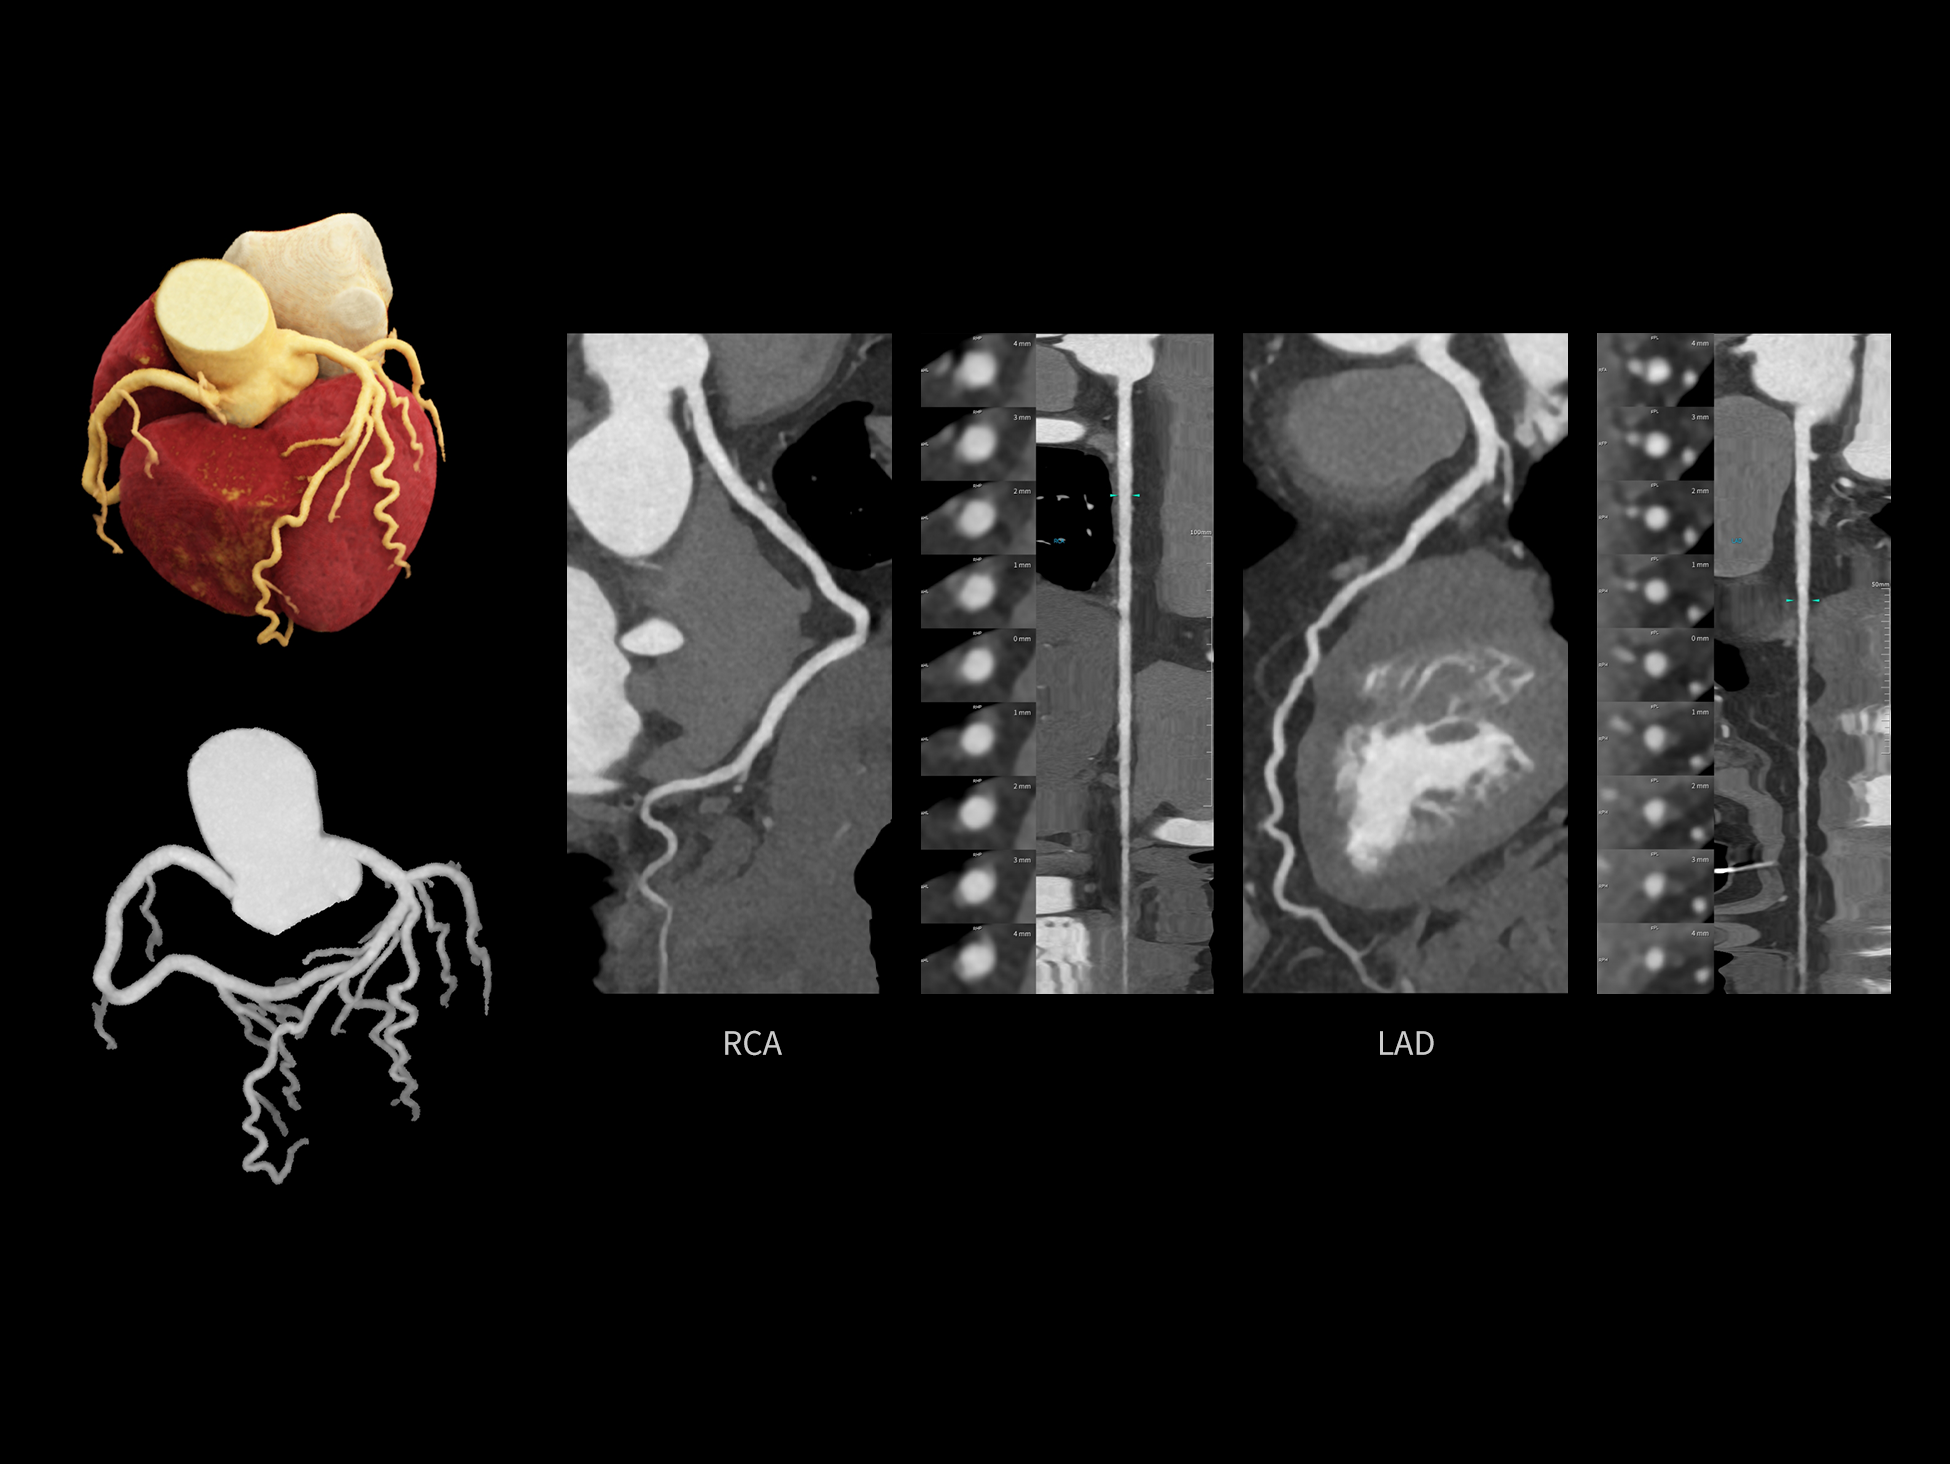

CardioCapture 2.0 通过“识别–追踪–建模–校正”的完整流程,精准分割心脏结构,动态追踪运动轨迹,并构建多时相运动场,最终实现冠脉、瓣膜、心肌及心室结构的同步校正,清晰洞见每一次心跳细微变化,真正将心脏动态掌握于毫秒之间。

CardioCapture 2.0 在目标时相前后重建多时相影像,通过深度学习网络精准提取冠脉中心线,进而建立时相间运动模型,实现对冠脉分段图像的精准运动校正。

CardioCapture 2.0 可对心肌、瓣膜及心室等结构进行同步运动校正。基于深度学习的心脏精细分割,实现了更完整的心脏全局信息提取,能有效抑制全心运动伪影,显著提升心脏细节的清晰度与诊断可靠性。

冠脉运动校正

全心结构运动校正

心脏成像,自由掌控